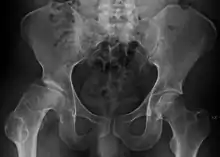

| Radiograph of a person with Legg–Calvé–Perthes disease | |

X-rays of the hip may suggest and/or verify the diagnosis. X-rays usually demonstrate a flattened, and later fragmented, femoral head. A bone scan or MRI may be useful in making the diagnosis in those cases where X-rays are inconclusive. Usually, plain radiographic changes are delayed six weeks or more from clinical onset, so bone scintigraphy and MRI are done for early diagnosis. MRI results are more accurate, i.e. 97–99% against 88–93% in plain radiography. If MRI or bone scans are necessary, a positive diagnosis relies upon patchy areas of vascularity to the capital femoral epiphysis (the developing femoral head).[12]